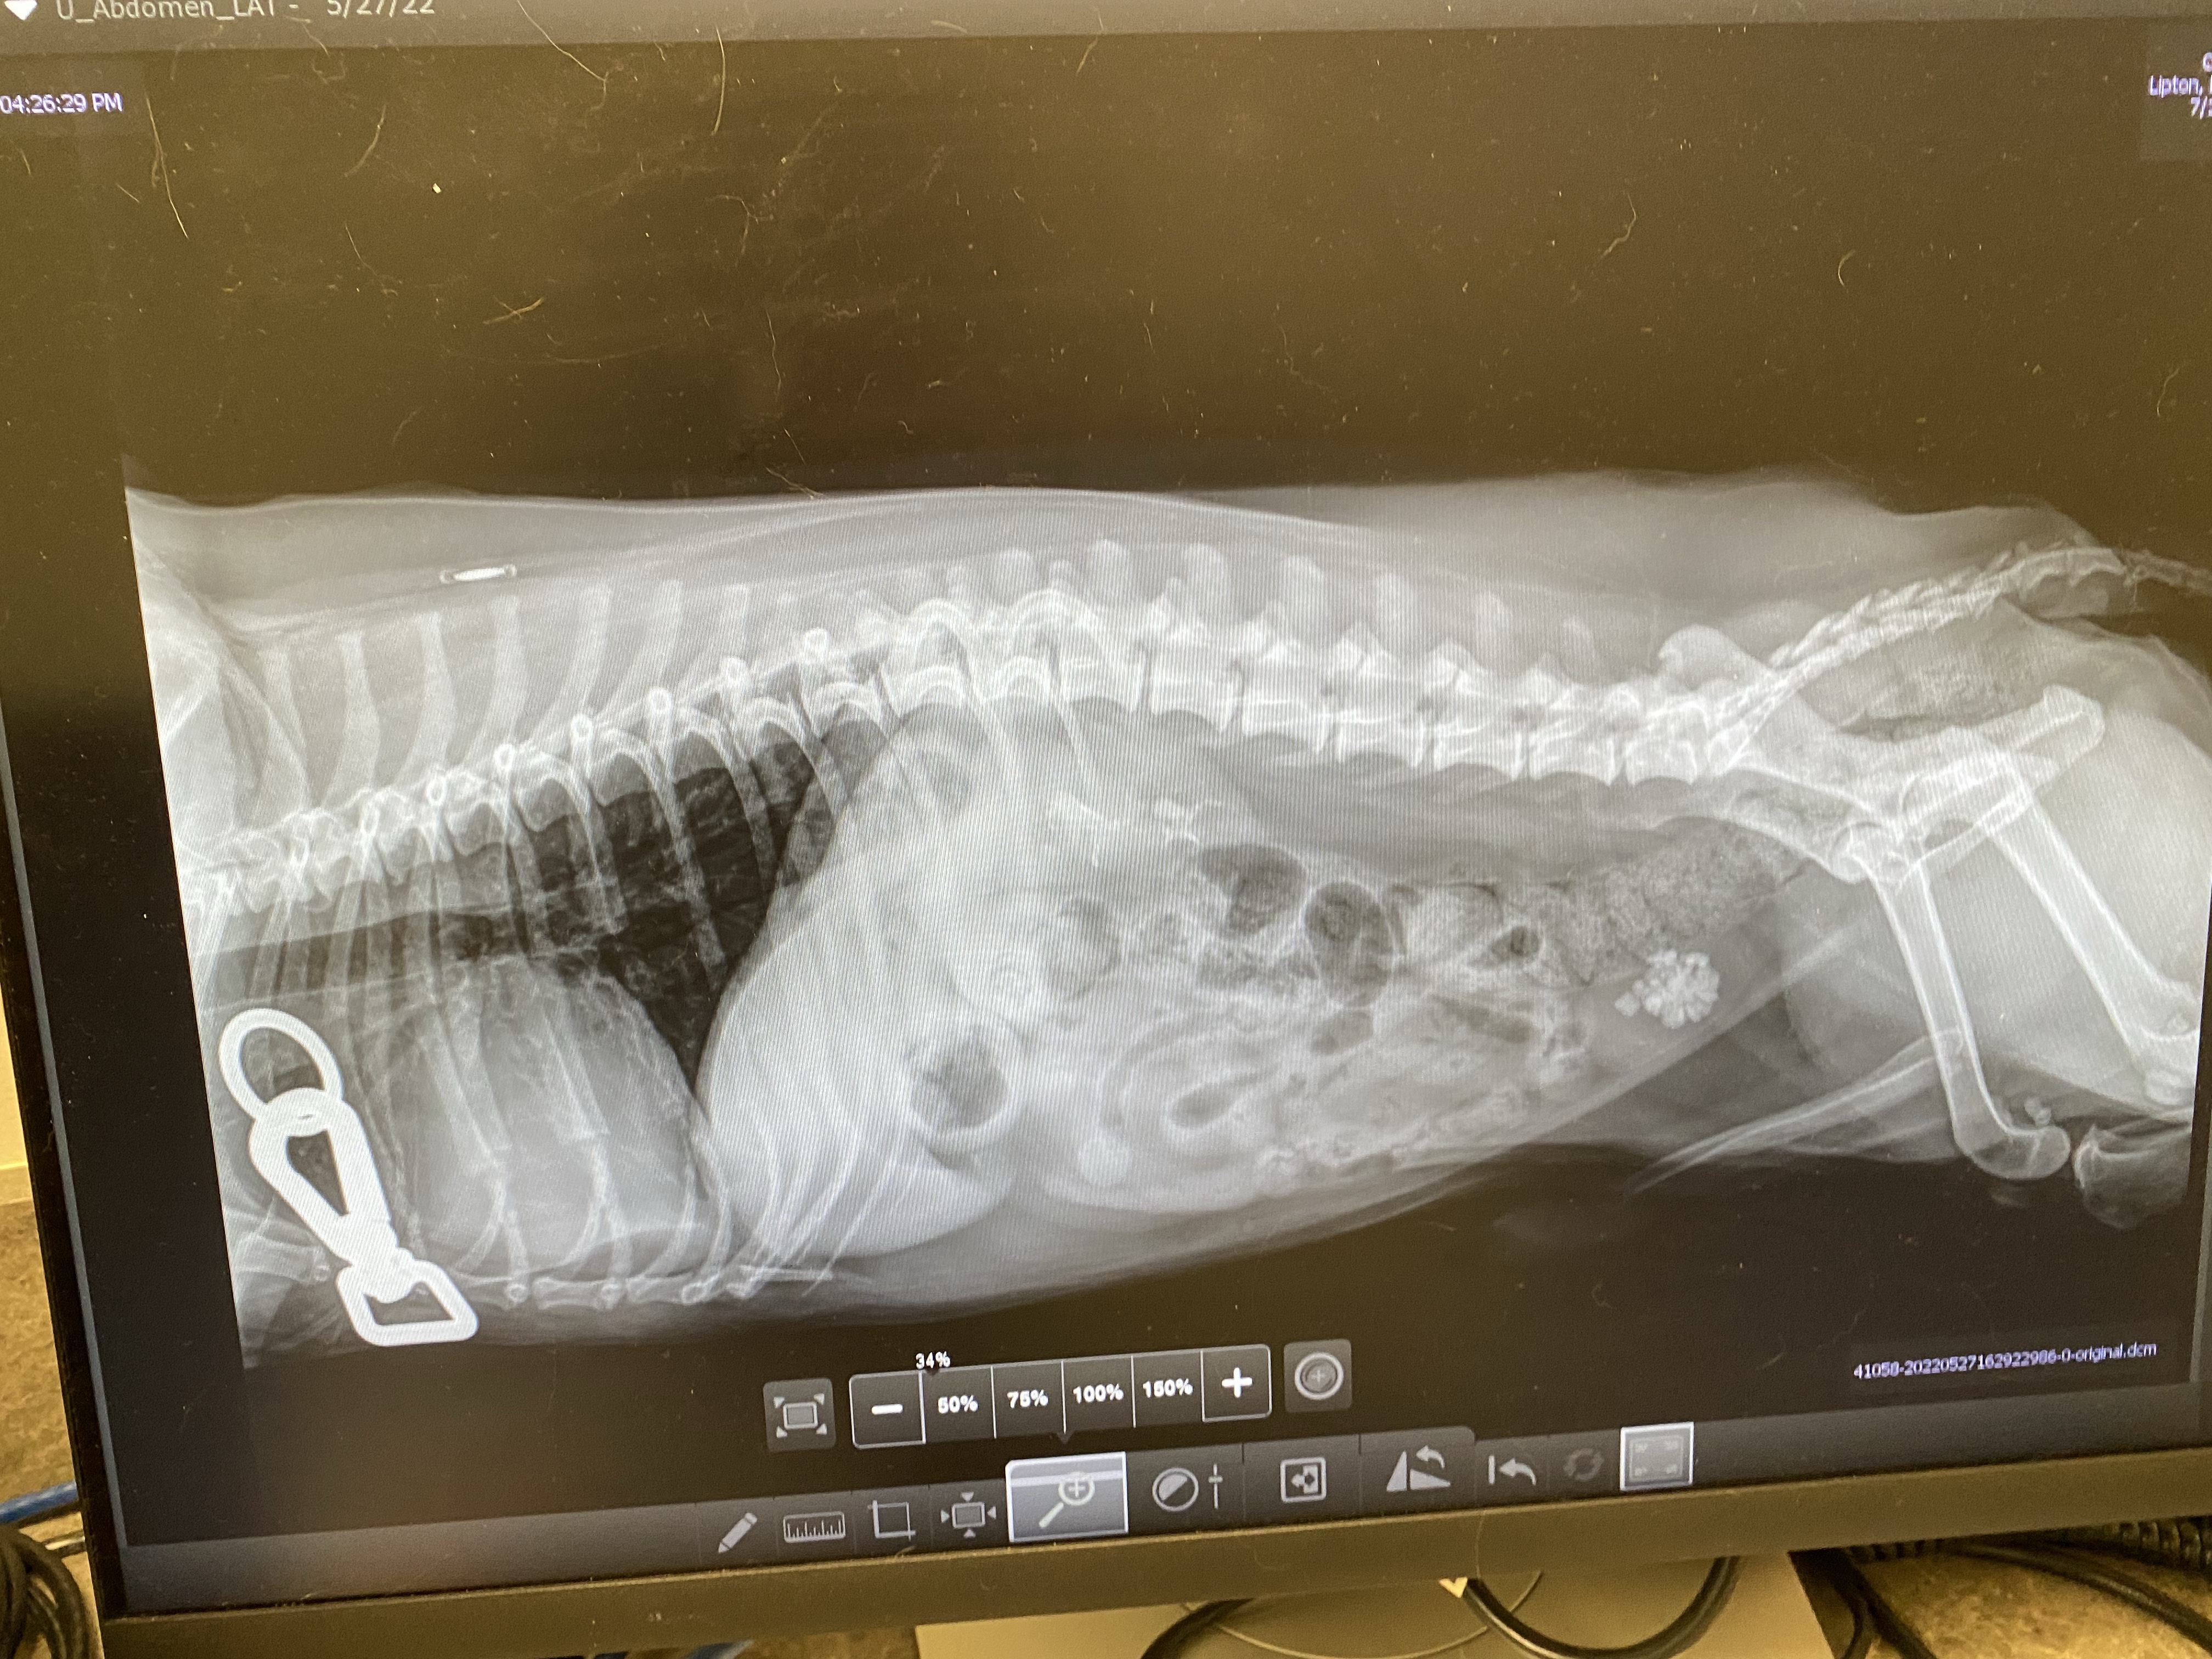

Third – and most critical at the moment – was the finding of BLADDER STONES, and a ton of them. Again we have no idea what caused all these stones, but the poor man has a ton in his bladder. Some theories are that the stones are caused by bacterial infection, body metabolism, previous disease, or dietary factors, like a lack of certain vitamins. Like kidney stones, there are several types: struvite, urate, xanthine, cystine, and calcium oxalate. Our hope is that these are struvite stones because they are the easiest to deal with.

I know your next question is how does one deal with the stones. There are several options.

- Dietary Dissolution

- Surgical Removal

- Non-surgical urohydopropulsion

- Ultrasonic dissolution

First, we are trying dietary dissolution. He is on a special Royal Canin Urinary SO diet and absolutely nothing else. The hope is that this food will begin to dissolve the stones. If nothing else, the vet hopes that it will at least make no new ones grow. He is also on an antibiotic (because he probably does have a UTI which is what we thought). Luckily, so far, he likes the food. I mix both wet and dry. We are making sure that he is passing urine every time he goes to the bathroom because the biggest concern, especially with a male, is a urinary blockage because of the stones. The vet said we need to take him to ER immediately if that happens. We are blessed that there is an Animal ER in town.

We go back on June 24th for another x-ray to see what is going on. He seems less lethargic and happier the last week, so maybe the food is working. Beat your drums for him. He is going to need all your prayers.